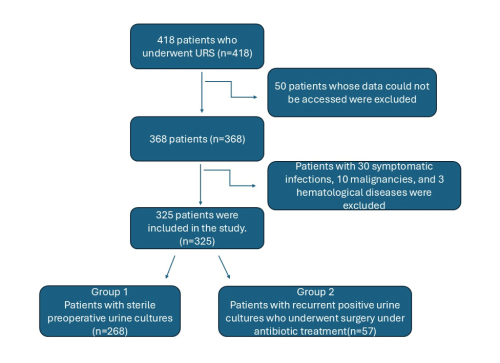

Hüseyin Aytaç Ateş, Muhammet Hilmi Enes Aracı, Yusuf Şahin, et al.

Urolithiasis is one of the most common conditions

encountered in urological practice, with its prevalence ranging

from 1% to 20%, depending on geographical, ethnic, dietary, and

genetic factors []. The high frequency of both newly diagnosed

and recurrent stone disease causes a significant psychosocial

and economic burden on patients, healthcare providers, and the

healthcare system, which cannot be overlooked []. Untreated

urinary tract stone disease significantly increases the risk of

acute and chronic renal failure, urinary tract infections, and other

complications associated with stones. A considerable number of

these stones necessitate active intervention [,].

Surgical treatment options include ureteroscopy (URS),

shock wave lithotripsy (SWL) and percutaneous nephrolithotomy

(PCNL) for most of the patients. It is known that among these

treatment options, URS has lower complication rates compared

to PCNL and higher stone-free rates compared to SWL []. With

technological advancements and the development of endoscopic

devices in more practical forms, ureteroscopy has gained

increasing application even in >2 cm diameter stones. Due to

its high treatment success and low morbidity, it is becoming an

increasingly preferred treatment option for the management of

ureteral and kidney stones [].

Although a substantial proportion of complications following

URS are minor and do not require further intervention, the

overall complication rate can reach up to 25% [,]. Among

these, infectious complications such as postoperative fever,

urinary tract infections, systemic inflammatory response

syndrome (SIRS), and urosepsis are particularly concerning

[-]. Preoperative bacteriuria is a known risk factor for

such complications, especially in patients with additional

risk factors including female gender, chronic diseases, higher

American Society of Anesthesiologists (ASA) physical status

classification system score, hydronephrosis, or infectious stones

[,]. While prophylactic antibiotics and careful perioperative

management can help reduce these risks [] a positive

preoperative urine culture remains a significant predictor of

postoperative infection and should be managed accordingly

[]. However, in patients with urinary tract stone disease,

achieving sterile urine cultures may not always be possible due

to persistent or recurrent bacteriuria and contamination [].

The belief that persistent urine culture positivity increases the

risk of surgical complications may heighten anxiety for both the

patient and the urologist. This concern often leads to repeated

antibiotic use, which contributes to bacterial resistance and may

increase patient's morbidity []. Additionally, delaying surgery

in pursuit of urine sterilization prolongs hospitalization, raises

healthcare costs, and may result in irreversible renal damage due

to ongoing obstruction []. Despite these challenges, there is

currently no clear consensus on whether URS should be delayed

until urine cultures are sterile or whether it can be performed

safely under targeted antibiotic therapy [].

In this single-center, retrospective study, we hypothesized that

URS can be performed safely in patients with persistent positive or

contaminated urine cultures, provided that appropriate antibiotic

treatment is administered. Therefore, we aimed to compare the

surgical outcomes of patients with sterile preoperative urine

cultures and those with persistent non-sterile cultures.